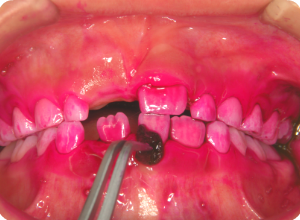

①まずは歯磨きがキチンと出来ているか、赤く染めて検査します。